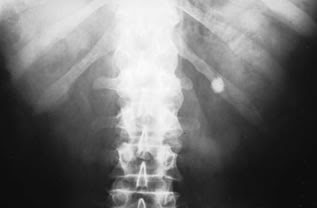

Cálculos renais pode ser uma das experiências mais dolorosas e estressantes da vida, basta ouvir qualquer pessoa que tenha sofrido com isso.

Os cálculos renais são certos resíduos que, por uma razão ou outra, começam a se acumular no rim e, por fim, tentam sair do corpo através do trato urinário.

Se a pedra é pequena o suficiente, talvez você consiga passá-la sem aviso prévio, mas uma pedra maior pode ficar presa no trato, causando dor imensa, sangue na urina e outros sintomas desagradáveis até que ela tenha passado.